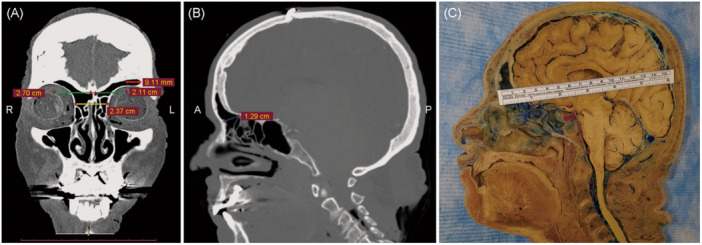

Methods: A descriptive study was performed, based on endoscopic and external cadaveric dissections. Quantitative analyses including horizontal, anteroposterior diameters, and exposure area were performed for each approach using the navigation system. Patients with various FS lesions were included and their data were collected and evaluated.

Results: Fifteen cadavers were analyzed. The average anteroposterior diameter on the midsagittal plane was 12.3 mm, distance from the midline to the lateralmost point was 21.8 mm on the right and 23.1 mm on the left side. The exposure area on the right side for Draf Ⅱa, and Draf Ⅱb were 64.6, 115.0 mm2 while on the left side were 67.0, 125.0 mm2. For Draf Ⅲ, the exposure area was 377.0 mm2. A total of 41 patients were included in the clinical correlation.